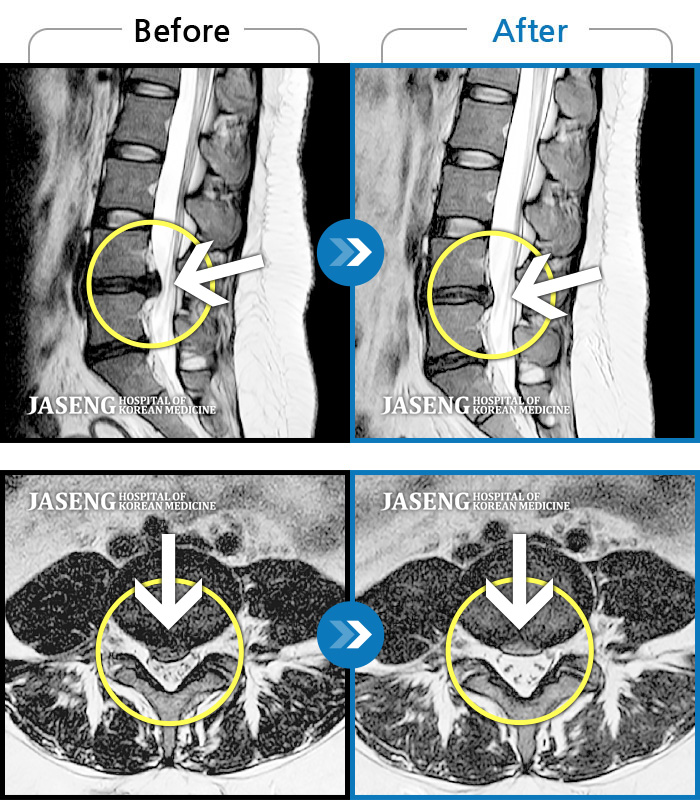

Before

After

허리 통증이 심하고, 양측다리 하지 쪽으로 땡기고 저려요.

2022.05.27 ~ 2022.10.28